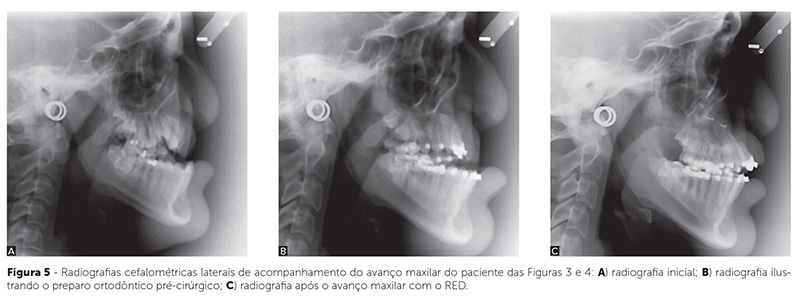

Protocolo

O protocolo de distração segue um ritmo de ativação entre 1 e 2mm por dia, dependendo da severidade da condição e da idade do paciente (nos pacientes jovens, pode não haver período de latência e o ritmo pode ser mais acelerado). Um período aproximado de uma ou duas semanas de distração é suficiente para a correção da maioria dos pacientes, quando é, então, iniciada a fase de consolidação óssea, compreendida entre quatro e oito semanas (Fig. 3, 4, 5). Há ocasiões em que surge uma resistência ao avanço maxilar, no final da fase ativa da distração. Nessas situações, opta-se pela montagem de um segundo sistema distrator na haste vertical. Providencia-se, assim, um sistema de tração com dois sistemas distratores, cada um apresentando dois parafusos para ativação (lado esquerdo e direito), significativamente mais forte e capaz de ultrapassar qualquer resistência oferecida pelos tecidos moles.

Tanto os pacientes com fendas quanto os que apresentam síndromes, experimentam estabilidade resultante dos tratamentos com, respectivamente, avanço da maxila e da face média (Fig. 8). A grande quantidade de formação óssea na área pterigomaxilar é o acontecimento crucial que favorece esse prognóstico. Além do volume, o tipo de osso lamelar denso — verificado em exame histológico e radiográfico11,16 — fortalece o prognóstico. Essa formação óssea local também possibilita espaço adicional para a erupção dentária (Fig. 9)28.